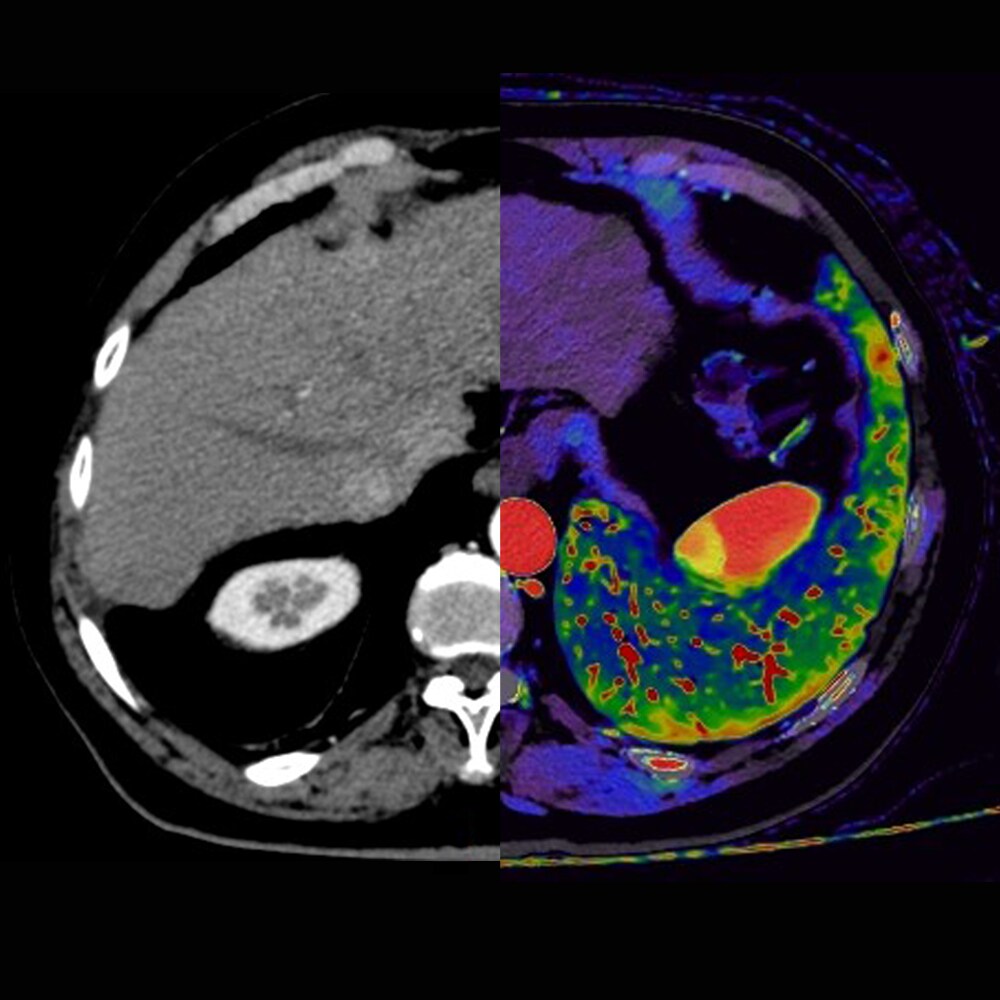

La Spectral CT rappresenta un’evoluzione della tomografia computerizzata (TC) che, grazie all’integrazione di una particolare tecnologia dotata di detettore spettrale Dual Layer, consente di ottenere immagini a colori ad alta definizione e ricche di informazioni, capaci di distinguere con precisione materiali e tessuti e di vedere le strutture anatomiche con un livello di dettaglio e di contenuto superiore.

Andrea Laghi, direttore del Dipartimento di Diagnostica per Immagini presso IRCCS Istituto Clinico Humanitas ha dichiarato: “Sulla base della mia esperienza posso dire che attraverso la tecnologia spettrale la TC si arricchisce di nuove possibilità, trasformandosi in uno strumento multiparametrico che si avvicina sempre di più alle potenzialità della risonanza magnetica. Grazie alle mappe di iodio e alla scomposizione dei materiali, possiamo analizzare i tessuti in modo più preciso, riducendo al tempo stesso la dose e il mezzo di contrasto. È una tecnologia sempre disponibile, che non modifica il flusso di lavoro e lascia al radiologo la libertà di scegliere come e quando sfruttarne le applicazioni per ogni paziente”.

A differenza delle altre tecnologie TC, la tomografia computerizzata spettrale utilizza fasci ad alta e bassa energia separati, a livello del detettore. La parte superficiale del detettore filtra la radiazione a bassa energia, mentre quella sottostante filtra la radiazione ad alta energia. Al contrario, le altre tecnologie oggi disponibili necessitano di due acquisizioni che vengono poi sovrapposte dal dispositivo. Inoltre, è dotato di un allestimento radioterapico che consente di monitorare l’evoluzione delle lesioni durante i trattamenti oncologici. Uno dei maggiori punti di forza di questa innovazione è la possibilità di effettuare acquisizioni spettrali utilizzando le stesse modalità operative già in uso: non è necessario programmare a priori l’esame in modalità “spettrale”, né modificare i protocolli usati abitualmente dal reparto di radiologia. Le immagini vengono acquisite come di consueto e, successivamente, è possibile accedere ai dati spettrali per ottenere informazioni aggiuntive, supportando il medico radiologo nell’interpretazione e nella diagnosi.